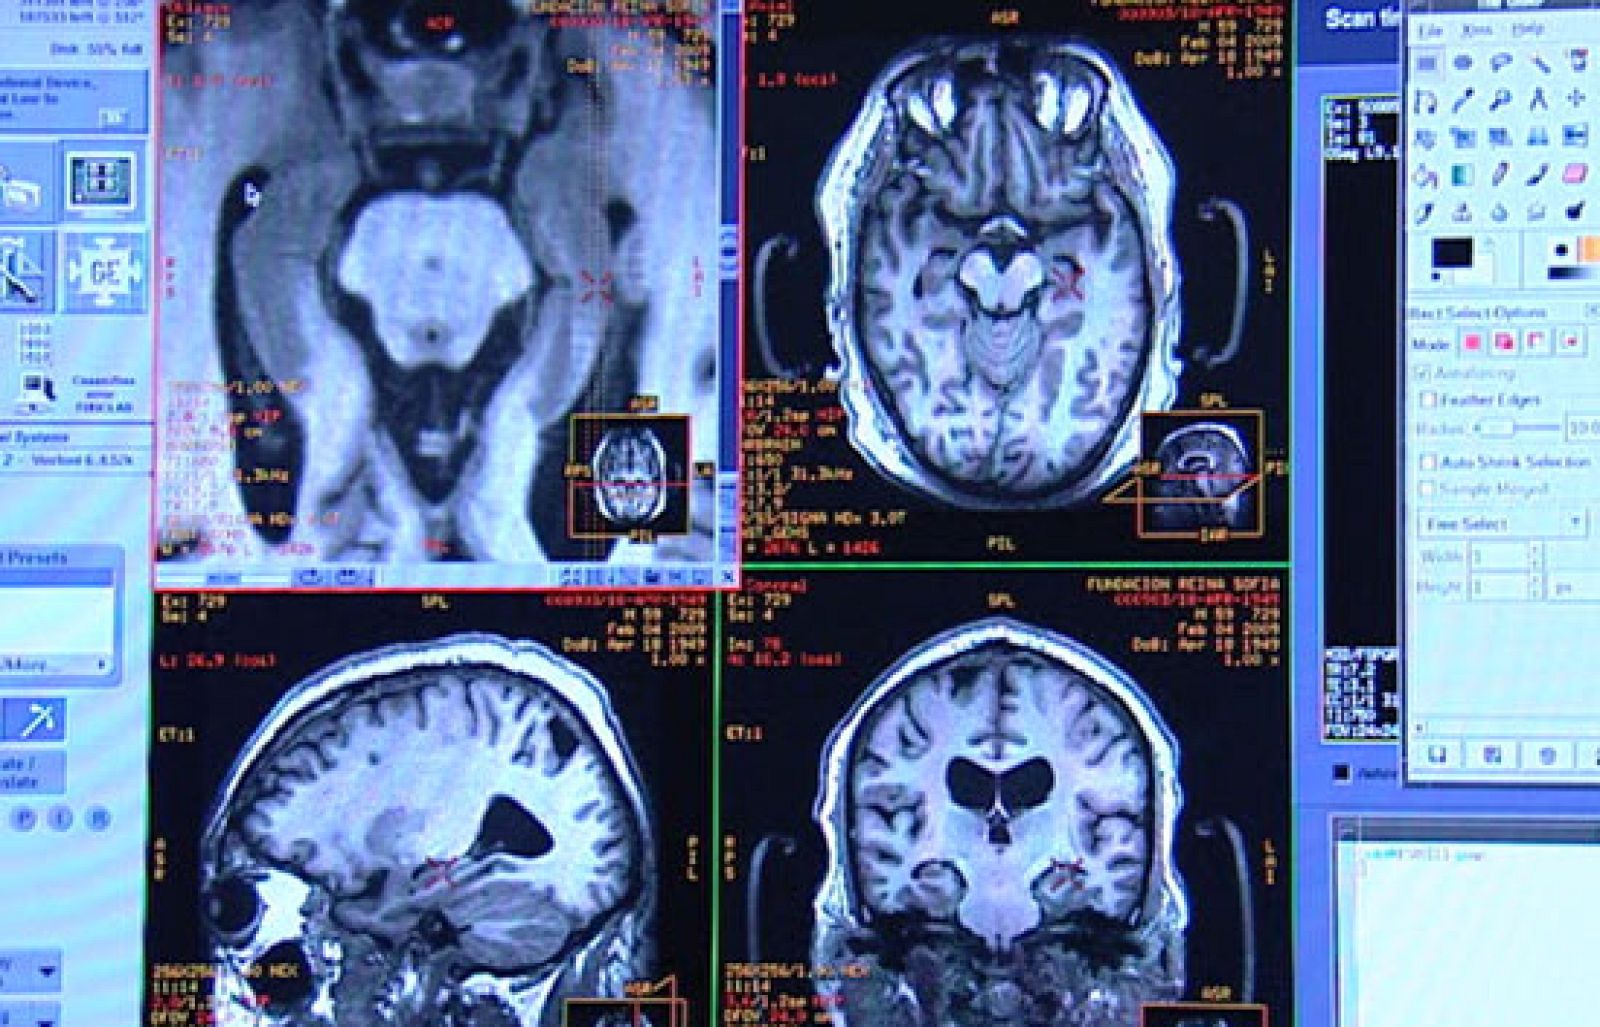

Descubrir cómo surge el alzheimer es unos de los retos de los investigadores. Al biochip que detecta precozmente la enfermedad, se une ahora una nueva técnica que utiliza potentes resonancias magnéticas. Esta técnica se va a probar en 700 personas que serán examinadas durante años.